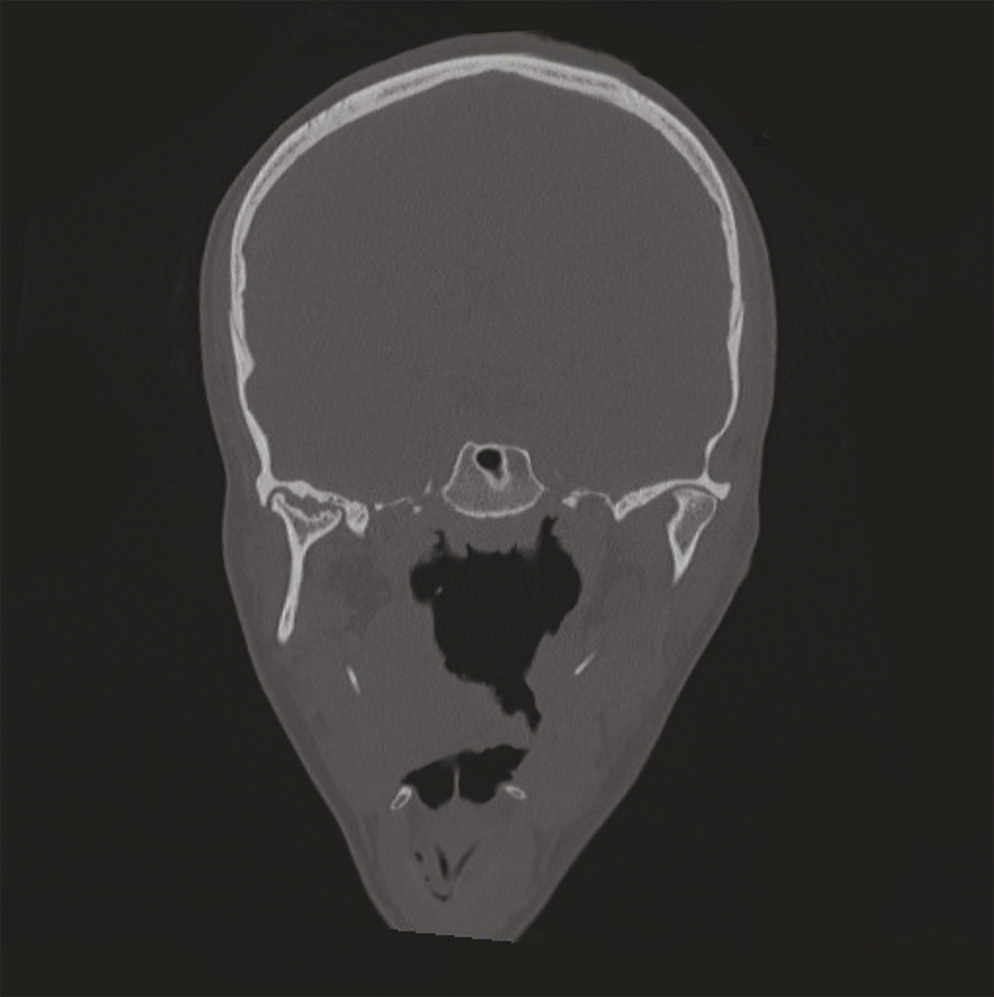

Face à une symptomatologie bruyante en échec de traitement fonctionnel, un bilan d’imagerie (orthopantomogramme, tomodensitométrie [TDM], imagerie par résonance magnétique [IRM]) est indispensable pour faire la part entre dysfonctions et pathologies remodelantes.

– une TDM non injectée en coupes fines (idéalement de 0,5 mm), acquis en relation centrée permettant d’obtenir la reconstruction tridimensionnelle des structures osseuses ;